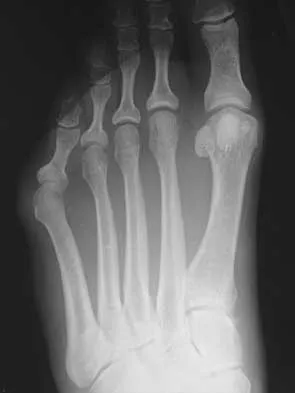

An active 47-year-old woman with rheumatoid arthritis reports forefoot pain and deformity and has difficulty with shoe wear. Examination reveals hallux valgus and claw toes. A radiograph is shown in Figure 10. What is the most appropriate surgical treatment?

Explanation

Rheumatoid arthritis commonly affects the metatarsophalangeal joints, which become destabilized with time resulting in hallux valgus and dislocated lesser claw toes. The result is metatarsalgia as the dislocated claw toes "pull" the fat pad distally. Severe hallux valgus reduces first ray load, which compounds the metatarsalgia because the load is transferred to the lesser metatarsal heads. First metatarsophalangeal arthrodesis restores weight bearing medially and corrects the painful bunion. Metatarsal head resection slackens the toe tendons to allow correction of the claw toes by whatever means necessary and decreases plantar load over the forefoot. Rheumatoid arthritis in the first metatarsophalangeal joint will continue to progress if osteotomies or a Lapidus procedure are performed. Keller resection arthroplasty increases transfer metatarsalgia and reduces push-off power during gait. Flexor-to-extensor tendon transfer of the lesser toes does not address the metatarsalgia and does not correct the dislocation of the metatarsophalangeal joint. Coughlin MJ: Arthritides, in Coughlin MJ, Mann RA (eds): Surgery of the Foot and Ankle, ed 7. St Louis, MO, Mosby, 1999, p 572.